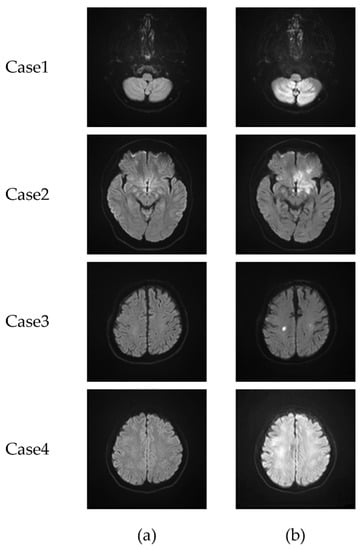

3.1. CycleGAN-Generated Images